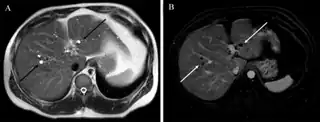

At CT scans, bile duct hamartomas appear as small, well-defined hypo- or isoattenuating masses with little or no enhancement after contrast administration.[4] At MRI, they appear hypointense on T1-weighted images, iso- or slightly hyperintense on T2-weighted images, and hypointense after administration of gadolinium based contrast-agent.[4] On imaging, multiple hamartomas may look similar to metastases or microabscesses.